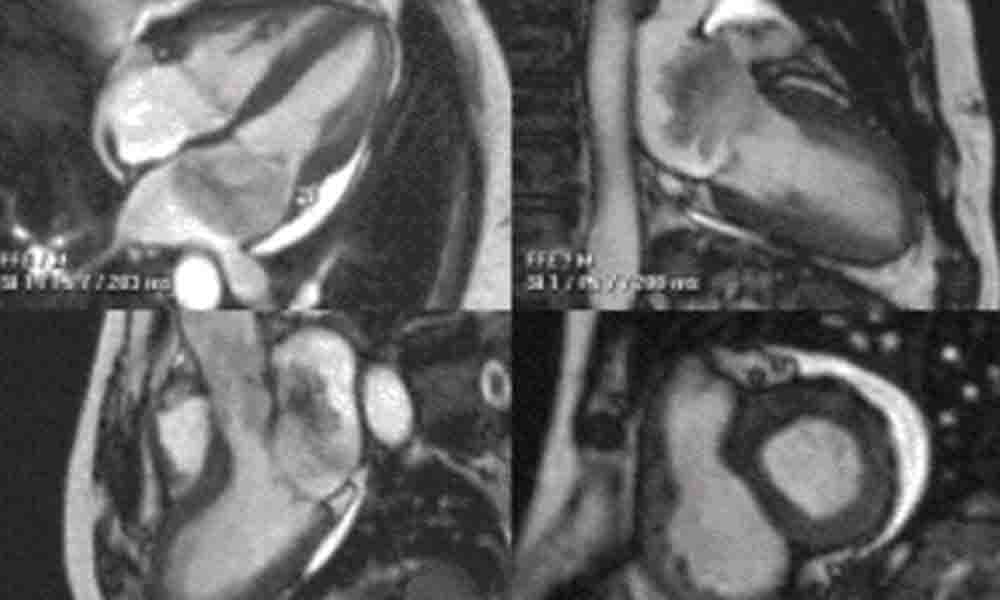

Cardiac MRI (CMR)

Designed and constructed by CMR experts, this app can report all CMR findings and machine settings. Global and regional function, cardiomyopathies, inflammatory disease, great vessel aneurysm and dissection are all supported.

Report Types:

- Cardiac MRI

- Coronary Angiography

- Stress Testing